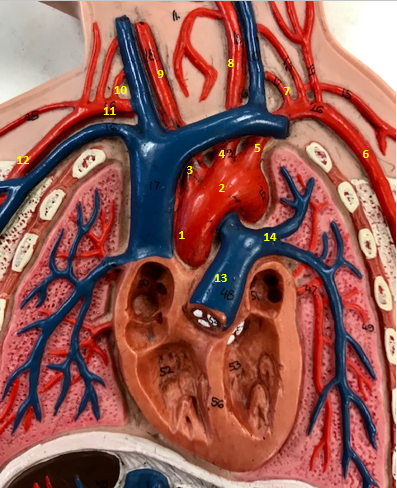

Aorta

Name #2

Brings blood out of left ventricle

Function of aorta

Brachiocephalic artery

Name #3

Supplies oxygenated blood to right arm shoulder neck and head

Function of brachiocephalic artery

Left common carotid artery

Name #4

Supplies oxygenated blood to left neck and head

Function of left common carotid artery

Left subclavian artery

Name #5

Supplies oxygenated blood to left arm shoulder

Function of left subclavian artery

Left axillery artery

Name #6

supplies blood to left armpit and upper limb

Function left axillary artery (6)

Left vertebral artery

Name #7

Supplies blood to brain and spinal cord

Function of left vertebral artery (7)

Left common carotid artery

Name #8

Supplies blood to left neck and head

Function of left common carotid artery (8)

Right common carotid artery

Name #9

Supplies oxygenated blood to right neck and head

Function of right common carotid artery (9)

Right vertebral artery

Name #10

Supplies blood to brain and spinal cord

Function of right vertebral artery (10)

Right subclavian artery

Name #11

Supplies blood to right arm and shoulder

Function of right subclavian artery

Right axillery artery

Name #12

Supplies blood to right armpit and upper limb

Function of right axillery artery (12)

Pulmonary trunk

Name #13

Bring blood out of right ventricle to lungs

Function of pulmonary trunk (13)

Left pulmonary artery

Name #14

Bring blood to left lung

Function of left pulmonary artery (14)